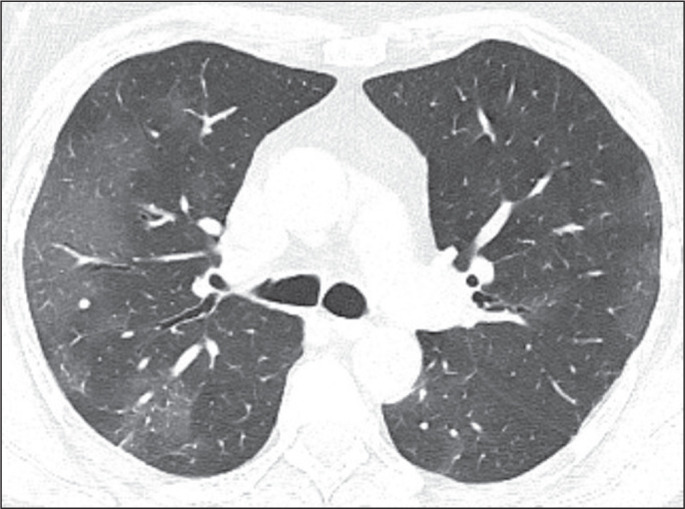

目的:评估2019冠状病毒(COVID-19)感染者典型CT扫描频率,并比较接种疫苗和未接种疫苗的人群。材料与方法:对2021年8月至2022年2月期间临床疑似COVID-19患者的病历进行回顾性研究。疫苗接种状态分为未接种/未接种(0或1剂)或已接种(2剂或更多剂)。在第一次胸部CT上所见的模式被定义为典型、非典型、不确定或正常,后三种模式被合并为非典型组。结果:二元logistic回归分析显示,完全接种疫苗的个体呈现典型CT模式的可能性低于未接种或不完全接种疫苗的个体(调整后OR = 0.19, 95% CI: 0.06-0.60)。结论:这一信息很重要,因为它表明,目前被认为是COVID-19典型的CT模式的频率低于疫苗可用之前的频率。因此,不再期望典型的CT表现。

Objective: To evaluate the frequency of the typical computed tomography (CT) pattern in individuals with coronavirus 2019 (COVID-19), comparing those who were vaccinated with those who were unvaccinated.

Materials and methods: This was a retrospective study of the medical records of patients with clinical suspicion of COVID-19 between August 2021 and February 2022. The vaccination status was classified as absent/incomplete (0 or 1 dose) or complete (2 or more doses). The pattern seen on the first chest CT was defined as typical, atypical, indeterminate, or normal, the last three patterns being combined to form what was designated the non-typical group.

Results: Binary logistic regression analysis showed that individuals with a complete vaccination status were less likely to present with the typical CT pattern than were those with an absent/incomplete vaccination status (adjusted OR = 0.19, 95% CI: 0.06-0.60).

Conclusion: This information is important because it demonstrates that the frequency of the CT pattern considered typical of COVID-19 is currently lower than it was before the vaccines became available. Therefore, the typical CT pattern is no longer expected.